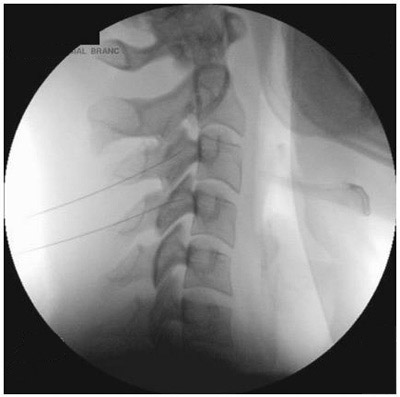

The doctor will then insert a thin needle directly into the

facet joint. Fluoroscopy, a type of x-ray, may be used to ensure the safe and proper position of the needle. A dye

may also be injected to make sure the needle is in the correct spot.

Once your physician is sure the needle is correctly placed, the medicine will be injected.